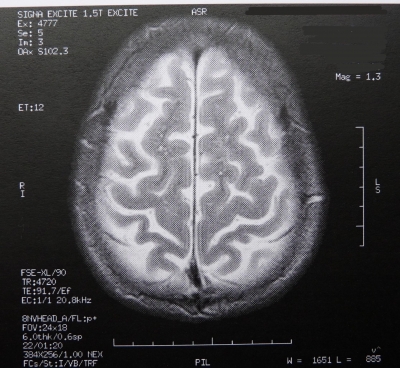

Sie sind hier: Startseite Nachrichten Gesundheit US-Studie: Tiefe Hirnstimulation kann Merkfähigkeit verbessern Bild: Dieter Schütz / pixelio.de

Bild: Dieter Schütz  / pixelio.de